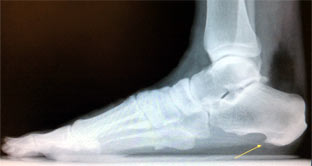

Ankle sprains are caused by a twisting injury or force on the ankle joint, often resulting in one or more ligaments of the ankle to be stretched or torn. Ankle injuries occur commonly while playing basketball, slipping on ice, and stepping incorrectly off of a curb. If not properly treated, ankle sprains can develop into chronic conditions. Symptoms include pain, swelling and bruising to the ankle and difficulty walking and participating in activities. X-rays are always taken in the office to rule out fracture and occasionally an MRI is ordered to evaluate the extent of injury to the ankle ligaments. Treatment includes rest, icing, stretching, bracing, MLS Laser therapy, physical therapy, and anti-inflammatories.